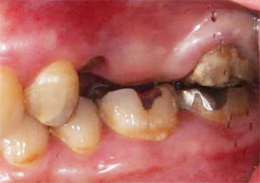

ショートインプラント使用し骨造成をしないグラフト術式

- 主訴

- 左上ブリッジの支台であった左上5を歯根破折でばっしとなり左上56の欠損となった

- 治療内容

- 抜歯から3ヶ月の治癒期間を経てCT撮影を行った結果、通常であれば上顎洞挙上手術の対象となるケースが多いが、ショートインプラントを用いることで大規模な骨造成お回避できることがわかった。2本ショートインプラント埋入

- 治療費用

- 900,000円(税別)

- 治療期間

- 5ヶ月